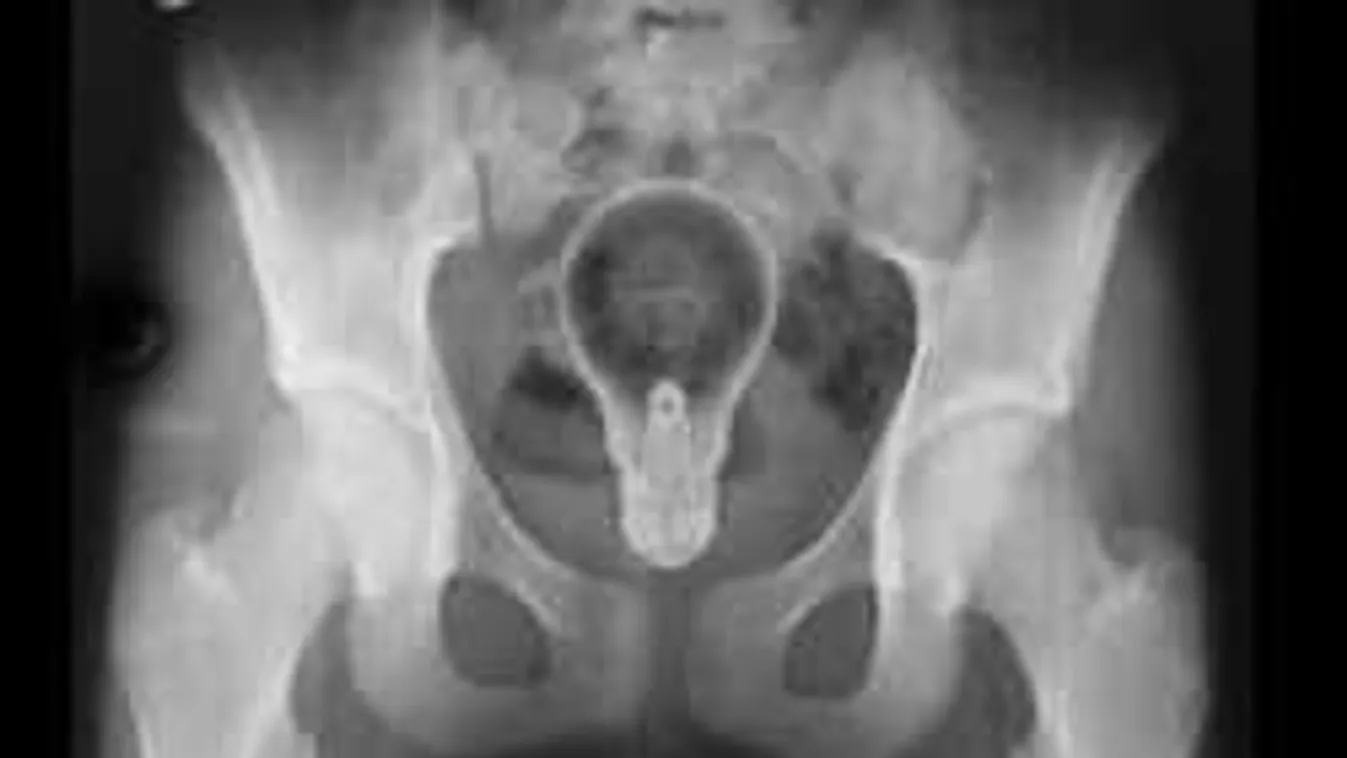

1. "Jó napot, doktor úr! Azt hiszem, bennem maradt egy villanykörte. Ki tudná szedni?"